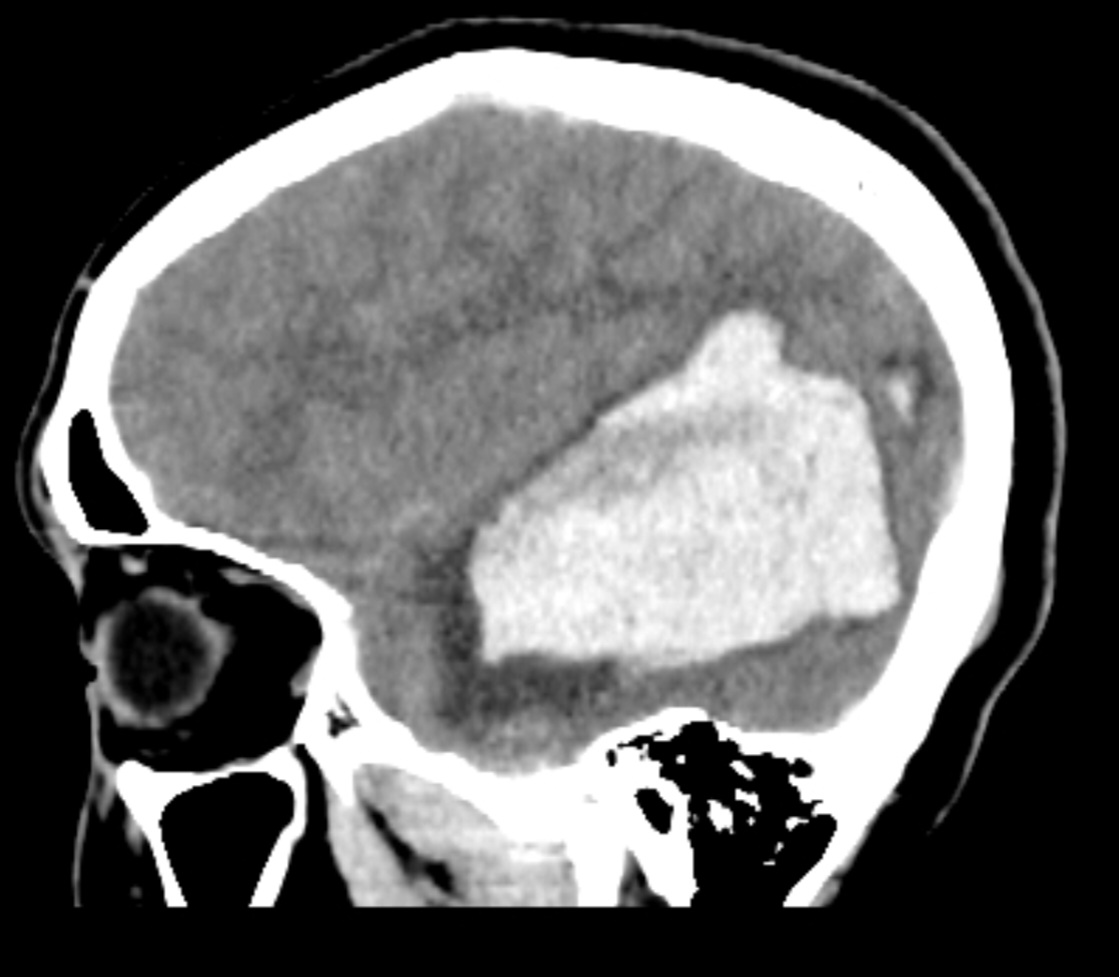

术后4小时CT复查术区干净,AVM已切除,动脉瘤夹闭良好

CTA显示:AVM已切除,动脉瘤夹闭良好